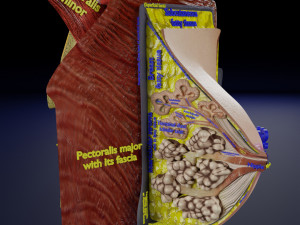

This is a 1:1 scaled model of right breast cut opened in sagittal plane to reveal its internal antomy and histology (schematic). The deeper parts and fascial layers are also depicted to give a very detailed approach to the model. The full layers starting from skin, nipple areola, till intercodtal muscles and ribs are also depicted.